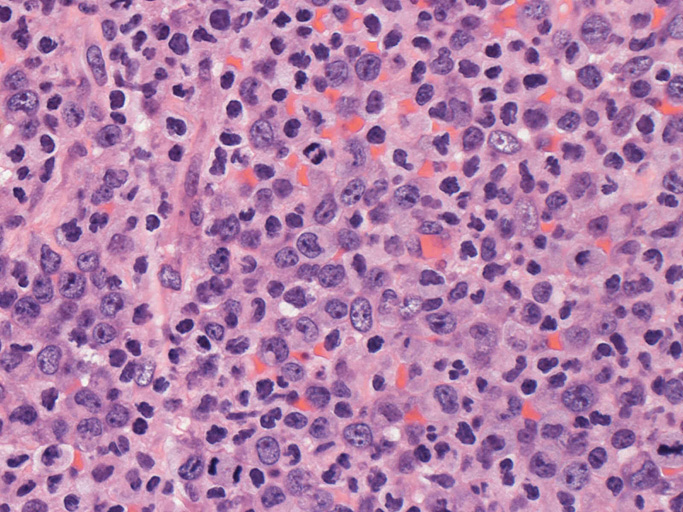

頸部リンパ節病理組織所見

いわゆるanaplastic large cellと呼ぶ多型または腎臓型核をもった大型細胞の増殖はみられない。centroblastに似る円形, 卵円形, わずかに切れ込みをもつ核をもつ大型細胞が索状または地図様に集ぞくし, 背景には淡明な細胞質としわのよったhypercrhomaticな核をもつ細胞がシート状に認められる。二種類の細胞がHEでは認められる。

ALK-positive ALCLのvariant, lymphohistiocytic variantが近いと考える